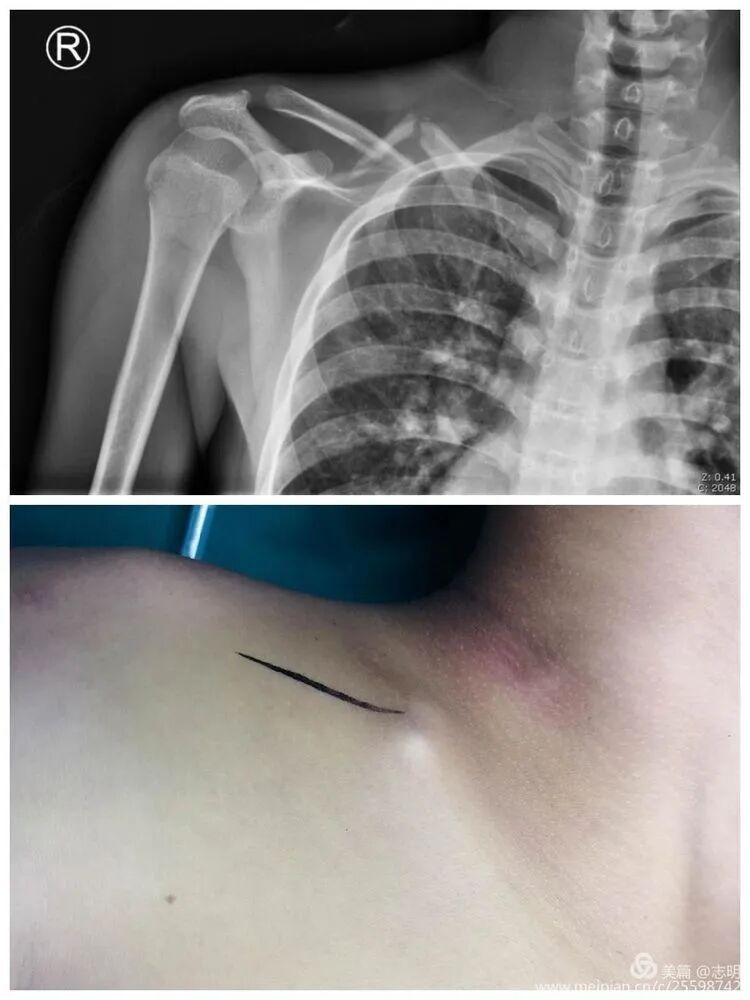

(Example of pre-operative imaging, likely an X-ray showing fracture).

(Initial fluoroscopic view of the fracture).(Another pre-reduction X-ray).

Clavicle fractures are among the most common skeletal injuries, accounting for approximately 2.6% to 10% of all fractures and up to 45% of shoulder girdle injuries. The vast majority, roughly 80% as noted in the seminal content, occur in the midshaft, a region also known as the diaphyseal segment. Historically, conservative management, primarily with sling immobilization, was the mainstay for most clavicle fractures, with operative intervention reserved for specific indications such as open fractures, neurovascular compromise, or floating shoulder. This approach, while avoiding surgical risks, often resulted in malunion, shortening, and residual cosmetic deformity, particularly in displaced adult fractures. For pediatric populations, especially those under 14 years of age, robust remodeling potential typically favors conservative treatment, as also highlighted in the seed content.

The clavicle, a superficial yet critical component of the shoulder girdle, is highly susceptible to fracture, accounting for 2-10% of all fractures and up to 45% of shoulder girdle injuries. Diaphyseal or midshaft clavicle fractures constitute the overwhelming majority, approximately 80%, of these occurrences. Historically, the management of most clavicle fractures leaned towards conservative measures, employing simple sling immobilization. This approach, while averting surgical risks, frequently resulted in undesirable sequelae such as malunion, symptomatic shortening, and aesthetic deformities, particularly in displaced adult fractures. Conversely, in the pediatric population, notably those under 14 years of age, the inherent robust potential for bone remodeling generally supports conservative treatment.